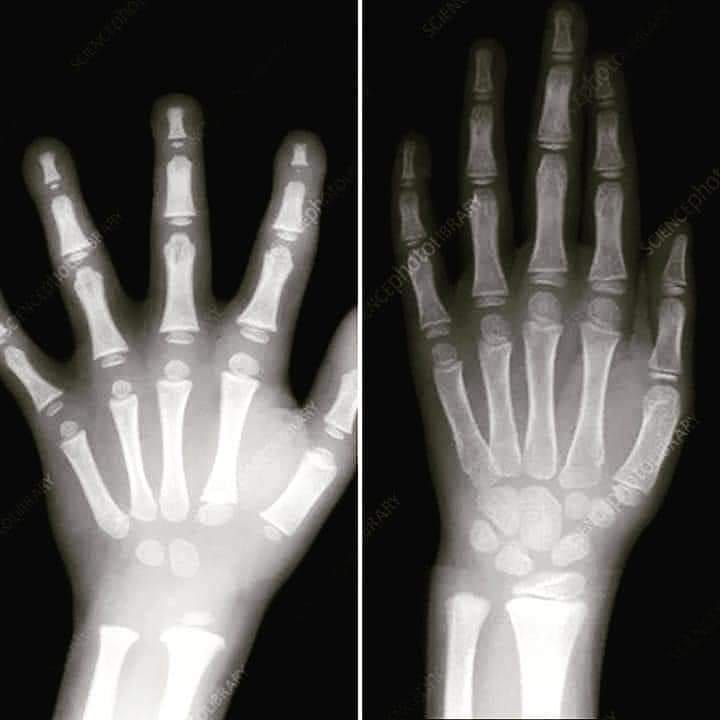

Στη παραπάνω εικόνα διακρίνεται η σημαντική διαφορά στην ανάπτυξη του χεριού ενός παιδιού προσχολικής ηλικίας (αριστερά) και ενός παιδιού 7 ετών (δεξιά).

Ο λόγος που ένα παιδί προσχολικής ηλικίας δυσκολεύεται να γράψει είναι το ότι τα χεράκια του δεν έχουν αναπτυχθεί και σχηματιστεί πλήρως.